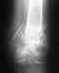

После того как на тренировке вывихнула косточку на стопе к врачу не обращалась,по-видимому произошло неправильное сращение и теперь спустя три года не могу носить узкую обувь и на каблуке...подскажите пожалуйста что делать?где это можно сделать? и сколько это будет стоить?